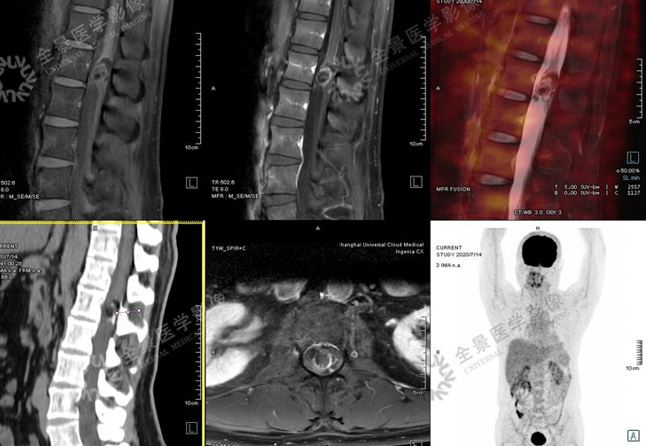

2. 神经系统

CT及MR平扫占位效应明显

畸胎瘤

√MR显示病灶与脊髓的关系,压脂序列呈低信号;

√CT可显示病灶内钙化,可见少许脂肪密度;